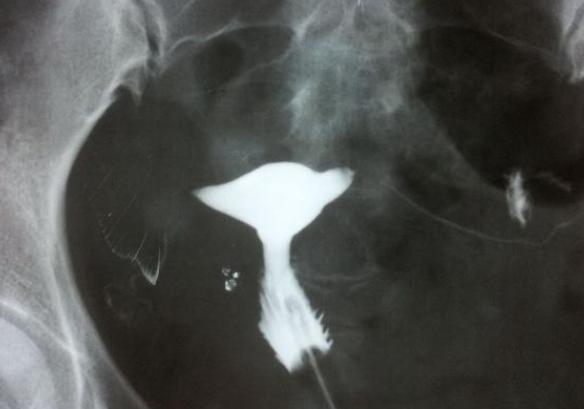

而输卵管造影则是一种通过X光或超声波来检查输卵管是否通畅的方法。这个过程需要将一种称为造影剂的特殊液体注入子宫内腔,并通过X光或超声波来观察其流动情况。